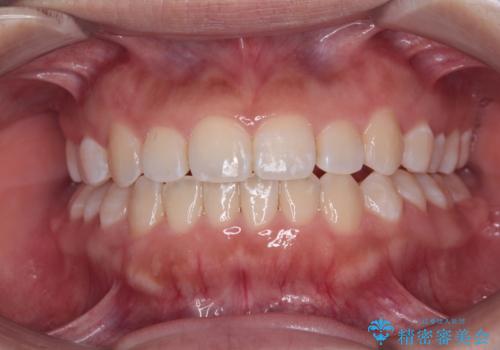

矯正後の後戻りで前歯にガタツキができてしまった インビザラインで改善

前歯のガタツキをインビザラインで改善